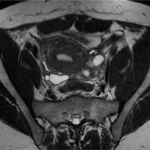

L’examen commence par des acquisitions en coupes standards pour avoir une vue d’ensemble des organes pelviens. S’ensuivent des images plus spécifiques, réalisées selon la pathologie recherchée, modulant les paramètres d’acquisition – pondération T1, T2, diffusion, etc. En cas d’injection de produit de contraste, de nouvelles séquences sont réalisées pour mettre en lumière les tissus anormaux.

Après l’examen, le radiologue analyse minutieusement les images obtenues à la recherche de signes pathologiques ou anomalies. Cette étape est cruciale pour aboutir à un diagnostic pelvien fiable. Le rapport d’IRM décrit les observations en termes d’anatomie, structure tissulaire, présence de masses, inflammations, ou modifications suspectes.

Le professionnel de santé doit maîtriser les nuances apportées par les différentes séquences pour distinguer, par exemple, un simple kyste bénin d’une tumeur ou détecter des signes précoces d’endométriose. Une corrélation avec l’historique médical du patient enrichit la lecture des images, ouvrant la voie à une orientation thérapeutique personnalisée.